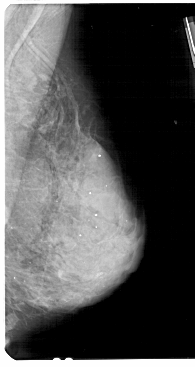

A_1936_1.LEFT_MLO

LEFT_MLO LINES 5491 PIXELS_PER_LINE 2836 BITS_PER_PIXEL 12 RESOLUTION 43.5 OVERLAY

FILE: A_1936_1.LEFT_MLO.OVERLAY

TOTAL_ABNORMALITIES 1

ABNORMALITY 1

LESION_TYPE CALCIFICATION TYPE AMORPHOUS DISTRIBUTION DIFFUSELY_SCATTERED

ASSESSMENT 4

SUBTLETY 1

PATHOLOGY BENIGN

TOTAL_OUTLINES 1

BOUNDARY